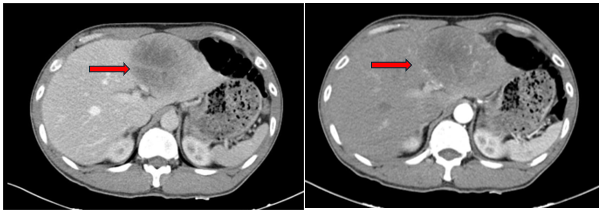

Case lâm sàng: Ứng dụng trí tuệ nhân tạo (Artificial intelligence – AI) trong chẩn đoán và điều trị sớm Ung thư phổi tại Trung tâm Y học hạt nhân và Ung bướu, Bệnh viện Bạch Mai

Theo GLOBOCAN 2022, ung thư phổi đứng đầu về số ca mới mắc (2.480.301 ca mới mắc chiểm 12.4%) và dẫn đầu số ca tử vong (1.817.172 ca tử vong chiếm 18.7%) trên toàn thế giới.  Tại Việt Nam tỷ lệ mắc ung thư phổi xếp thứ ba 13,5% lệ tử vong...